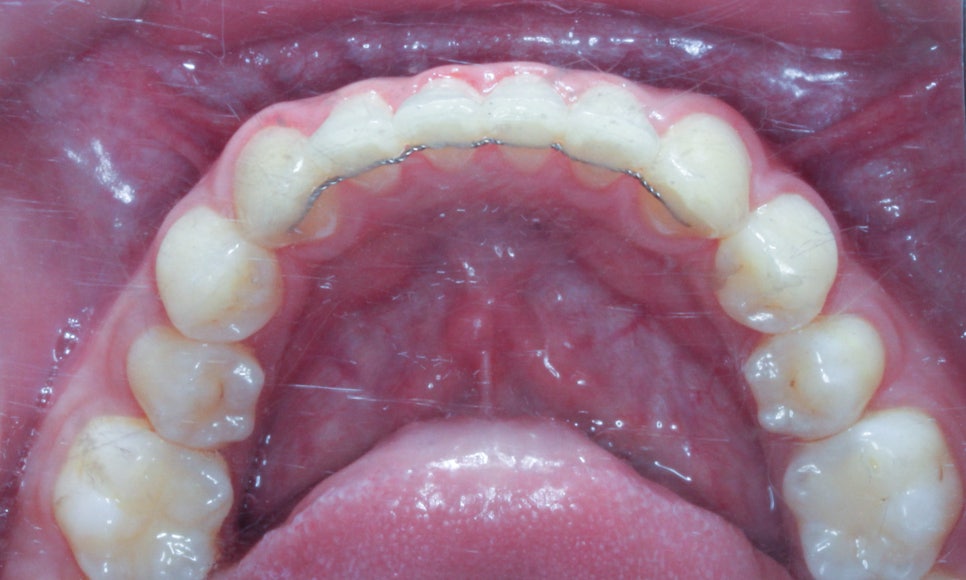

상악과 하악의 안쪽면 역시

가지런하게 배열된 모습이네요

특히 치아 크라우딩이 발견되었던

하악의 전치부가 예쁘게 정돈된 모습이죠?